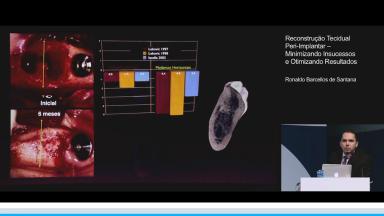

Reconstrução Tecidual Peri-Implantar – Minimizando Insucessos e Otimizando Resultados

O objetivo da aula é ambientar o ouvinte na área de manejo, manutenção e regeneração dos tecidos ósseos visando a colocação de implantes osseointegrados. Demonstrando os problemas ósseos existentes nos sítios de colocação de implantes e reconhecendo que existem muitas técnicas e materiais para a regeneração destes tecidos, o apresentador estabelece parâmetros comparativos entre os itens baseados em evidências científicas de qualidade. Visando minimizar o insucesso da terapia de regeneração óssea e da colocação de implantes o ouvinte precisa entender que já a partir de abordagens iniciais precisa decidir entre manutenção e regeneração óssea, e quando desta última conhecer os materiais e técnicas existentes com os seus limites para esta terapia.